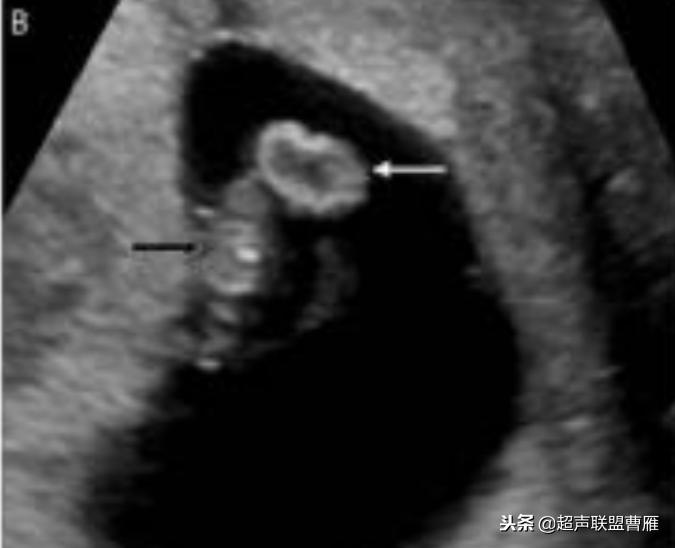

· 卵黄囊不规则或钙化:出现囊壁钙化或者增厚等形态改变以及囊壁缺损,提示 卵黄囊功能衰退与营养障碍,预示妊娠结局不良。一般情况下,出现钙化通常胚胎已停育。

钙化卵黄囊6.6mm,一周后胚胎死亡

卵黄囊回声增强,预后不良

卵黄囊钙化